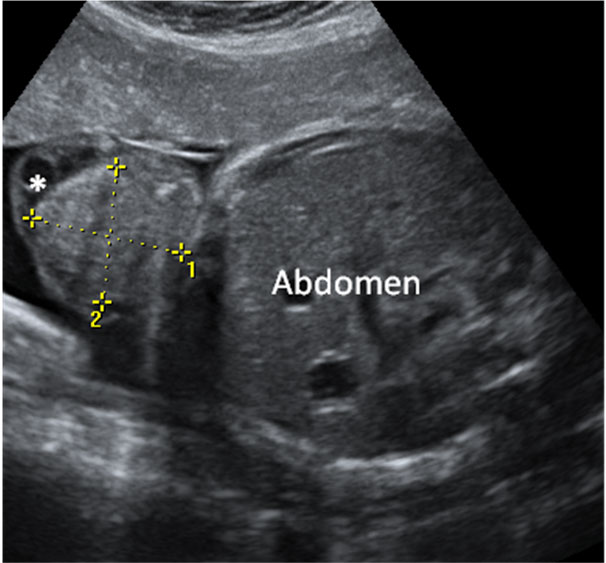

En la imagen ecográfica podemos ver el corte de la cabeza fetal donde se muestra la medición de un ventrículo cerebral aumentado de tamaño (o ventriculomegalia).